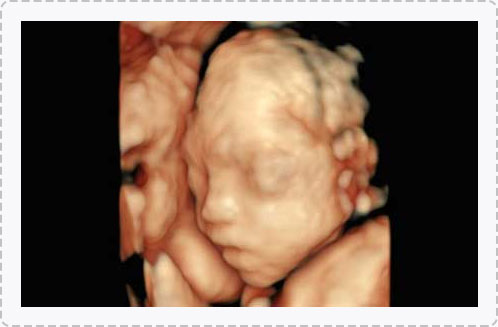

四维彩超能够直观、立体地显示人体器官的三维结构以及动态,实时地观察立体结构,被广泛用于检查胎儿发育状况,立体观察胎儿在子宫内发育情况的同时,还能够清晰显示胎儿在子宫内的动态,让准爸妈们一起观看宝宝在妈妈肚子里的动作、神态,还可将这个过程制作成光碟保存,让宝宝能够拥有完整的0岁相册,留下珍贵的纪念。

宝宝的0岁写真,是值得每个父母珍藏的。